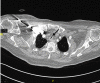

CT of the thorax shows the sternoclavicular joint with tracheal stenosis.

Figure 2 CT of the thorax shows the sternoclavicular joint with tracheal stenosis.